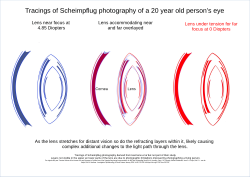

imgi_146_250px-Human_Lens_Scheimpflug_layers.svg.png